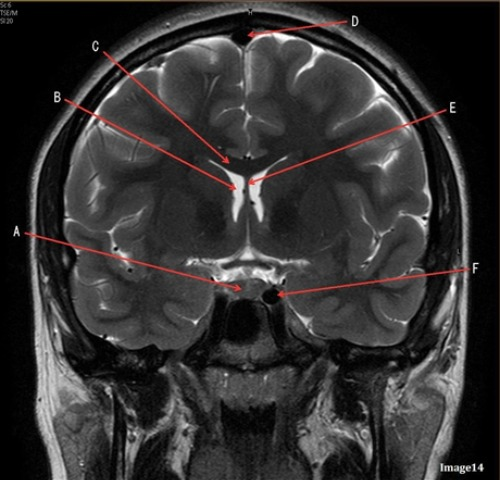

Image 11 is an example of a _______ weighted sequence acquired in the _______ scan plane.

D. T2; Coronal

Letter D in Image 14 is pointing to:

D. Sagittal sinus

Letter B in Image 14 is pointing to:

C. Lateral ventricle

Letter C in Image 14 is pointing to:

A. Corpus callosum

Letter A in image 14 is pointing to:

D. Pituitary gland

Letter F in image 14 is pointing to:

D. Internal carotid artery

Letter E in Image 14 is pointing to:

E. Fornix